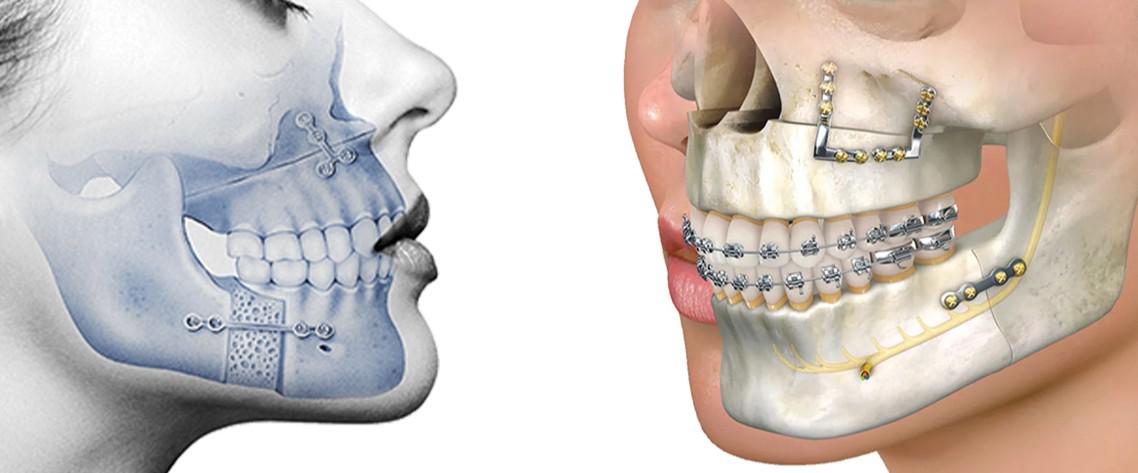

قبل جراحة الفكين والأسنان في جدة، يمكنك توقع إجراء فحص شامل يتضمن تقييمًا سريريًا دقيقًا مع طبيب جراحة الفم والفكين، بالإضافة إلى تصوير بالأشعة السينية البانورامية، وأحيانًا الأشعة المقطعية ثلاثية الأبعاد (CBCT) للحصول على صورة واضحة لعظام الفك والأسنان والأعصاب.

هذه المرحلة تساعد الطبيب على تشخيص مشكلات إطباق الأسنان، بروز أو تراجع الفك، وموقع جذور الأسنان بدقة، مما يضمن تحديد مدى تعقيد جراحة الفكين والأسنان بدقة.

الإطباق (عضة الأسنان)

من أهم ما يتغير فعليًا بعد جراحة الفكين هو الإطباق أو عضة الأسنان.

قبل الجراحة قد يعاني المريض من عضة مفتوحة، أو عضة عميقة، أو تقدم الفك السفلي أو العلوي، ما يسبب صعوبة في المضغ وعدم تناسق الأسنان عند الإغلاق.

خلال جراحة الفكين يتم تعديل موضع الفك العلوي والسفلي بحيث تلتقي الأسنان في وضع صحيح ومدروس، وغالبًا بالتعاون مع علاج تقويم الأسنان.

النتيجة بعد الجراحة هي عضة أسنان مستقرة ووظيفة مضغ أفضل، مع تقليل تآكل الأسنان ومشكلات المفصل الفكي الصدغي على المدى البعيد، وهو عنصر رئيسي في تقييم نتائج قبل وبعد جراحة الفكين من الناحية الوظيفية.

تعالج جراحة الفكين في جدة مشكلات بروز أو تراجع الفك، عدم تطابق الأسنان، بروز الذقن أو صغرها، ومشكلات الابتسامة اللثوية، ما ينعكس مباشرة على شكل الفك السفلي والعلوي والوجنتين والذقن.

يقوم جرّاح الفكين بدراسة دقيقة للوجه باستخدام صور شعاعية ثلاثية الأبعاد وتحاليل عضوية لتحديد مقدار التعديل المطلوب، بحيث يكون التغيير متناسقًا ولا يبدو مصطنعًا.